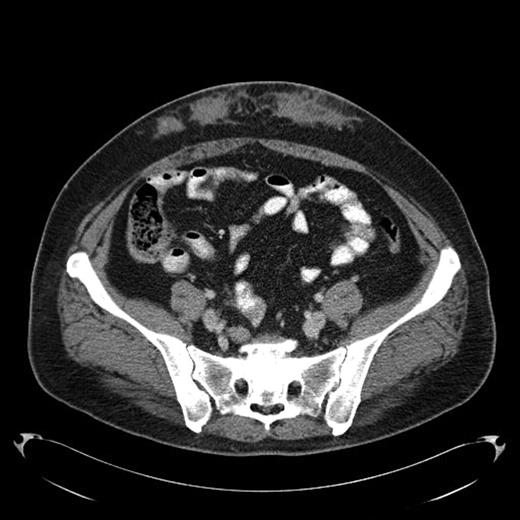

Amyloid infiltration in subcutaneous tissue of lower abdomen at insulin injection site

A 43-year-old female diagnosed with diabetes mellitus in 1986 after acute pancreatitis secondary to hypertriglyceridemia presented to our hospital in December of 2008 with a 2 year history of low grade fever of 99-100F. This was associated with chills and fatigue. Over the same time period she had noticed anterior abdominal wall nodularity, particularly at sites where she has been injecting her insulin. Her insulin requirement had also increased from a total of 60 units of NPH in a day to 170 units per day. Because of the subcutaneous nodularity at the site of injection a decision was made to switch the site of the insulin which resulted in lower blood glucose level and subsequently significant decrease in her insulin requirement to 120 units a day. This suggested poor absorption from the infiltrated site. At our clinic laboratory data showed normal white count of 5.4 × 10(9)/L with normal differential, normal hemoglobin of 12.9 g/dL with an ESR of 11 mm/hour, creatinine of 0.8 mg/dL and C-reactive protein of less than 3. As part of the work up for fever of unknown origin a CT-scan of the abdomen was obtained which showed infiltrative lesion in the anterior abdominal subcutaneous tissue with few calcifications Fig 1 & 2. Biopsy of the anterior abdominal wall nodular infiltrate was performed. Tissue cultures came out negative for infection. The biopsy showed eosinophilic material positive with Congo red staining and showing apple green birefringence when viewed under polarized light. Immunohistochemical staining showed this to be negative for AA, AL, or TTR amyloidosis. Liquid chromatography tandem mass spectrometry (LC MS/MS) detected peptides representing apolipoprotein E, apolipoprotein A-IV, SAP and Insulin. The amyloid deposits stained positive with anti-insulin. The presence of peptides from insulin and immunohistochemical reactivity with an anti-insulin antibody indicated that the amyloid deposits were caused by insulin injection at this site. Work up for systemic amyloidosis including serum protein electrophoresis with immunofixation was negative for a monoclonal protein. Quantitative immunoglobulins were within normal range. Her 24-hour urine protein was 65 mg within normal range. Her serum free light chains were unremarkable. Echocardiogram did not show any evidence of infiltrative cardiomyopathy. This was therefore consistent with localized insulin induced cutaneous amyloidosis. The recommendation was to change the insulin type and to rotate the insulin injection site. Because of occasional hemorrhage and pain the long term plan will be to surgically remove the amyloid deposits.